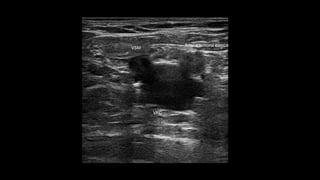

Figura 4. Safena interna en espacio safeno en el muslo.

Figura 4. Safenainterna en espacio safeno en el muslo. una later se denom el 40% d del muslo la unión s nodo bas fácilment con los v interna q Es muy i cialmente post-ope